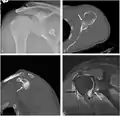

CT scan showing a bony Bankart lesion at the antero-inferior glenoid

3-D CT reconstruction of a bankart lesion which occurred post anterior shoulder dislocation. This subject's humerus remains mildly superiorly subluxated. Fracture marked by a black arrow.